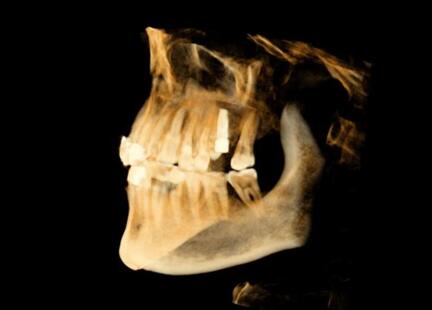

該系統(tǒng)用于口腔種植手術(shù)的術(shù)前計(jì)劃和術(shù)中引導(dǎo),通過對三維醫(yī)學(xué)影像的虛擬可視化應(yīng)用,采用專門的種植手術(shù)方案規(guī)劃軟件在三維模擬環(huán)境中進(jìn)行合理的種植方案設(shè)計(jì),結(jié)合精確的紅外光學(xué)定位技術(shù),實(shí)現(xiàn)手術(shù)器械、醫(yī)學(xué)影像和人體空間位置的融合。整個(gè)手術(shù)過程系統(tǒng)實(shí)時(shí)呈現(xiàn)病人解剖結(jié)構(gòu),全程監(jiān)控種植位點(diǎn)、角度、深度,從而實(shí)現(xiàn)精確種植。

運(yùn)用計(jì)算機(jī)三維重建與可視化技術(shù),清晰展現(xiàn)患者口內(nèi)解剖結(jié)構(gòu),保證了復(fù)雜病例的成功率。

導(dǎo)航病例1:上前牙缺失

患者信息:年輕,女性

主訴:上前牙殘根拔除術(shù)后六周,要求種植修復(fù)

現(xiàn)病史:患者因牙列不齊行正畸治療,約六周前正畸結(jié)束,并拔除上前牙殘根,要求種植修復(fù)。

檢查:21牙缺失,缺牙區(qū)牙齦狀況良好,無紅腫潰瘍,唇側(cè)牙槽骨豐滿度不足,近遠(yuǎn)中及齦頜距離可,原有過渡義齒佩戴良好。上下前牙淺覆頜覆蓋。全口衛(wèi)生良好。

種植體選擇:3.3*12mm士卓曼骨水平種植體

導(dǎo)航病例2:左上后牙缺失

患者信息:55歲,男性

主訴:患者牙缺失半年余,現(xiàn)要求種植修復(fù)